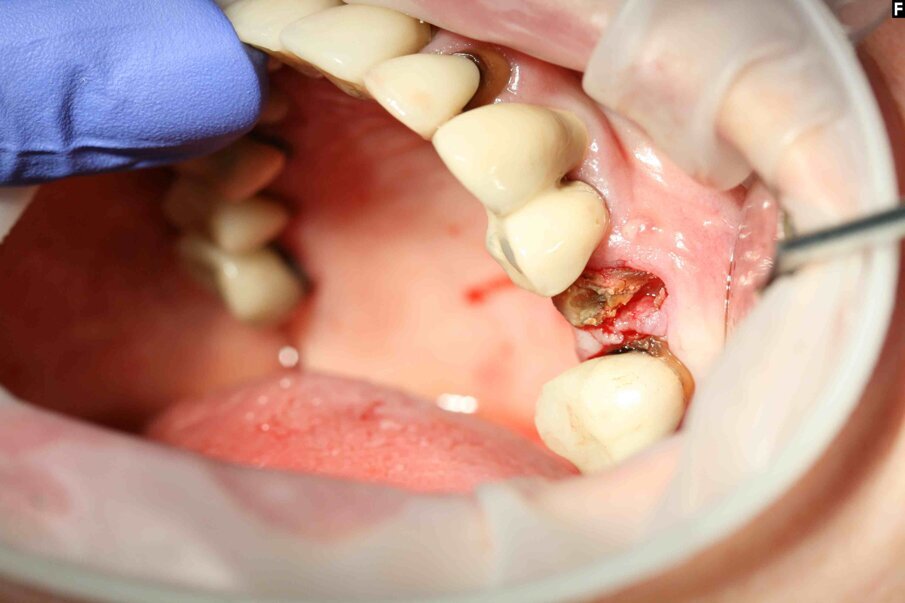

Fig. 6: The crown was fractured during luxation.

Luxator P4, with its extremely sharp dual-edge blade, was used at the beginning, followed by Luxator P1 once more space had been created. Although the blades of these sophisticated instruments are reinforced with a titanium coating, they should only be used to cut the periodontal ligament and never to elevate the tooth.

When the extraction had been completed, the alveolus was scraped and thoroughly flushed clean with physiological saline solution to prevent infection.